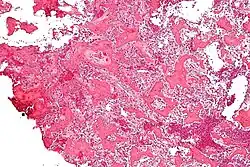

Histological findings

On histological examination, osteoid osteoma consists of a small (< 1.5–2 cm), yellowish-to-red nidus of osteoid and woven bone with interconnected trabeculae, and a background and rim of highly vascularized, fibrous connective tissue. Varying degrees of sclerotic bone reaction may surround the lesion. Benign osteoblastoma is virtually indistinguishable from osteoid osteoma. The usual appearance included a fibrovascular stroma with numerous osteoblasts, osteoid tissue, well-formed woven bone, and giant cells. The osteoblasts were generally small and regular in shape.[7]